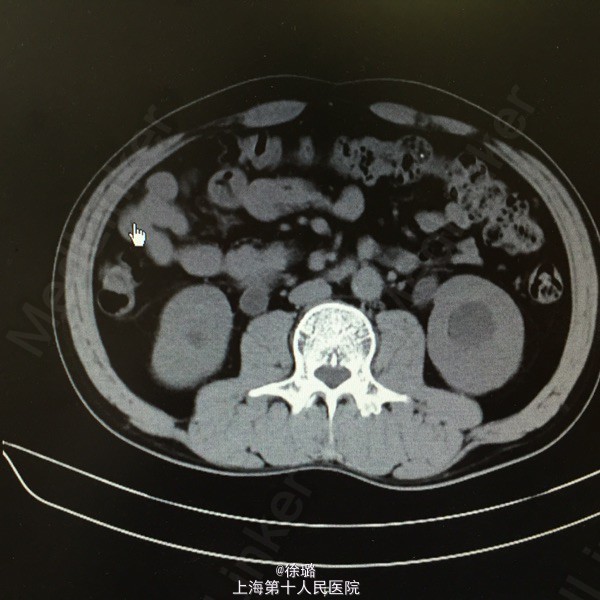

患者XXX,男,52岁。 主述:腰部酸胀不适半年余。 病史:患者半年前始无明显诱因出现腰部酸胀不适,左侧腰部酸胀稍明显,无恶心呕吐,不伴发热、黄疸、腹泻、黑便及肉眼血尿,症状轻,未诊治,今患者至当地医院查体,查B超示:双侧输尿管扩张伴肾积水,双侧输尿管上段结石。患者为进一步治疗,来我院就诊,拟“双侧输尿管上段结石”收住入院。

查体:双肾区无明显膨隆,左肾区无明显压痛,叩击痛可疑阳性,右肾区无明显压痛,叩击痛阴性,左侧输尿管走行区下段叩击痛阳性,右侧输尿管走行区下段叩击痛阴性,膀胱区无充盈,无压痛,尿道口无红肿。前列腺指检:前列腺未及增大,质韧,无明显结节,压痛阴性,指套无血染。 辅检:B超示:双侧输尿管扩张伴肾积水,双侧输尿管上段结石。尿路平片:1.双侧输尿管上段走行区致密影,考虑输尿管结石可能。2:盆腔耻骨联合上方投影区钙化影,前列腺钙化?请结合其他检查。3.CT:两侧输尿管上段结石,致其上输尿管及肾盂肾盏明显扩张积液。